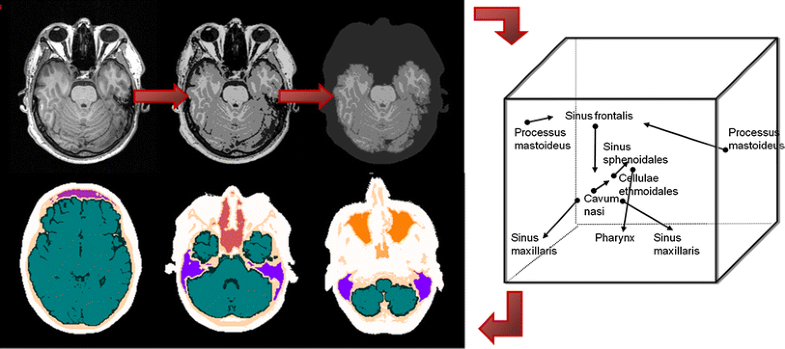

Steps in a template-based attenuation correction approach for brain [14]: The MR template is warped to match the individual MR image using SPM. The obtained transformation matrix is applied to warp the attenuation map template to generate an individualised attenuation map to which the coil attenuation map is added. The attenuation correction factors are obtained by forward projection

Principles of the direct knowledge-based segmentation approach for attenuation correction in brain studies presented in [31]: The input image (top left) is classified (top middle) and postprocessed to separate the extracerebral region (top right). The extracerebral region is segmented utilising class properties and relative positions of the regions (right). Segmented cavities and bone regions are the frontal sinus (mauve), the nasal cavity/ethmoidal cells/sphenoidal sinus (dark red), the maxillary sinuses (orange) and the pharynx (amber), the mastoid process (light blue), bone (light pink), brain (green) and CSF (dark green) tissue, and extracerebral soft tissue (white) (bottom)